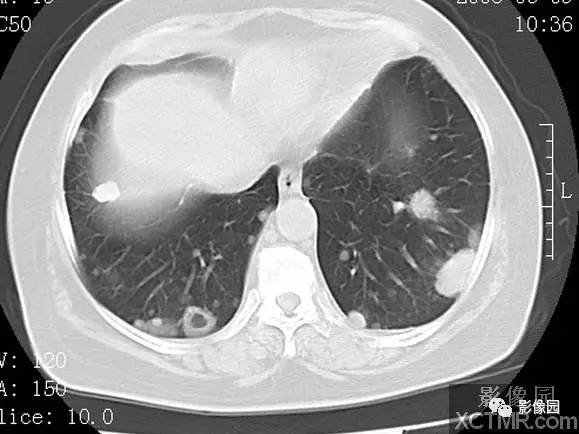

子宫内膜癌双肺转移1例CT

【临床病史】:患者,女 58 岁。 医学百科网 | YxBaike.Com

病理学检查:子宫内膜中分化乳头状腺癌 肿物侵达浅肌层伴累及一侧卵巢一侧卵巢:成熟性囊性畸胎瘤,一侧输卵管组织(-) 医学百科网 | YxBaike.Com

【影像图片】CT图像

【影像表现】:双肺内多发大小不一转移瘤,瘤体可见空洞及钙化。 医学百科网 | YxBaike.Com

【影像诊断】:子宫内膜癌双肺转移。

【诊断要点】:肺内转移瘤出现空洞及钙化改变的多见于鳞癌及粘液性腺癌。 医学百科网 | YxBaike.Com